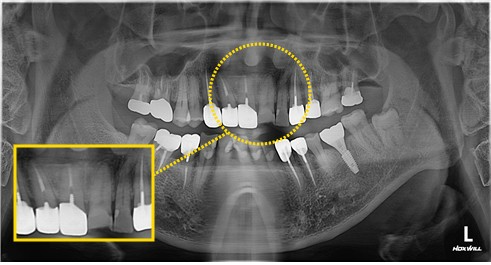

# 21, 22 치경부 마모증이 심하고 사이 충치까지 존재해 크라운 치료가 제일 심미적이겠지만, 필요한 부분만 제거하고 레진수복치료를 하였습니다.

#21.22 C.RF 절단면 RF 설명드림.